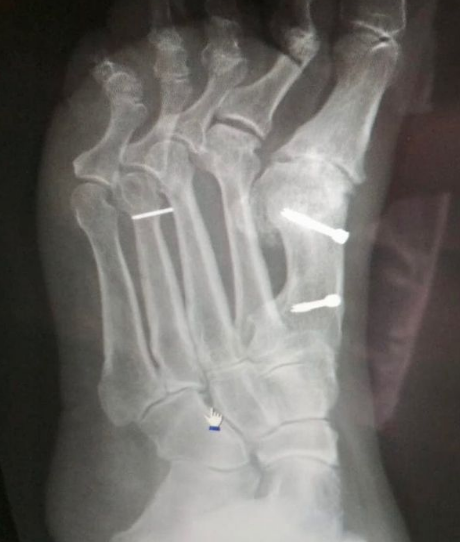

Несколько лет назад женщину прооперировали в связи с серьёзной деформацией ступни. На 2, 3 и 4 пальцы ей поставили спицы. Во время их извлечения одна из спиц сломалась, и обломок внушительного размера остался в ноге. Со временем ситуация усугубилась, пациентка почти перестала ходить.

«В отделении травматологии стационарного отделения №2 Люберецкой областной больницы прошла операция по извлечению «блуждающего» обломка металлоконструкции из ступни поступившей пациентки. После оказания медпомощи женщина вновь смогла свободно передвигаться», - говорится в сообщении.